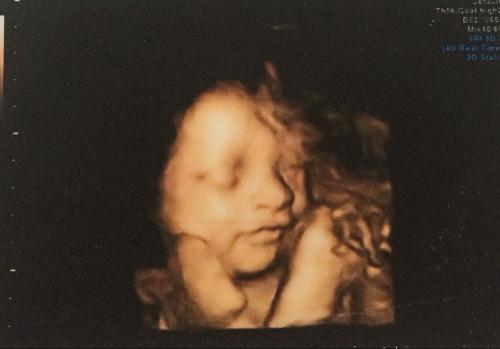

2,三维是在二维的基础上增加了另外一个空间轴,可以形成静态的立体图像。

3,四维又是在三维的基础上又增加了一个空间轴,形成了动态的立体图像。

二维是普通B超,图像呈黑白两色。三维、四维呈土黄色,很多人以为彩超彩超肯定是彩色的,其实并不是,之所以称为彩超只是因为会用彩色标注心脏、血流等指标。

二维视察到的只是平面图像,三维视察到的则是静态的立体影像,而四维就厉害了,能视察到动态的立体影像。

而且三维比之二维更加全面,清晰。四维比之三维又更多方位,更多角度,能实时地视察胎儿的动态立体结构。